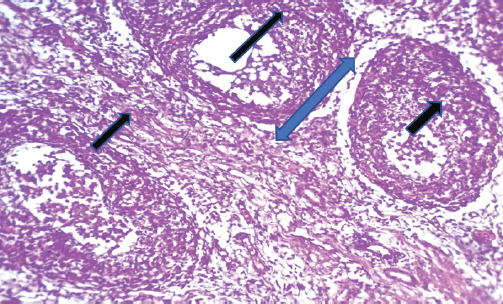

目的:从疑似感染的肉鸡养殖场中鉴定和检测重组传染性法氏囊病病毒(IBDV)。材料与方法:取肉仔鸡脾、法氏囊72份标本。在用于典型的PCR分子研究之前,对组织进行组织学检查。结果:该菌株被命名为IBDV ASPVB。基于PCR、测序和部分a段和b段的系统发育分析,伊拉克的IBDV ASPVB菌株被鉴定为一种新的重组菌株。相比之下,片段B来自其他田间重组菌株。感染该菌株可能导致轻微的临床症状,但对淋巴器官造成严重损害,导致免疫反应受损。结论:由于持续的进化,本研究表明伊拉克的IBDV表现出广泛的组织学、遗传和表型变异;据我们所知,这是伊拉克首次报道重组IBDV。

Materials and methods: The broiler yielded 72 samples, including the spleen and bursa of Fabricius. The tissues underwent histological examination before being used in a typical PCR molecular investigation.

Results: The strain was subsequently termed IBDV ASPVB. The IBDV ASPVB strain in Iraq has been identified as a novel reassortant strain based on the results of PCR, sequencing, and phylogenetic analysis of partial segments A and B. Segment A of this strain is derived from the highly pathogenic IBDV strain. In contrast, segment B is derived from other field reassortant strains. Infection with this strain might result in minor clinical symptoms but substantial damage to lymphoid organs, leading to compromised immunological responses.